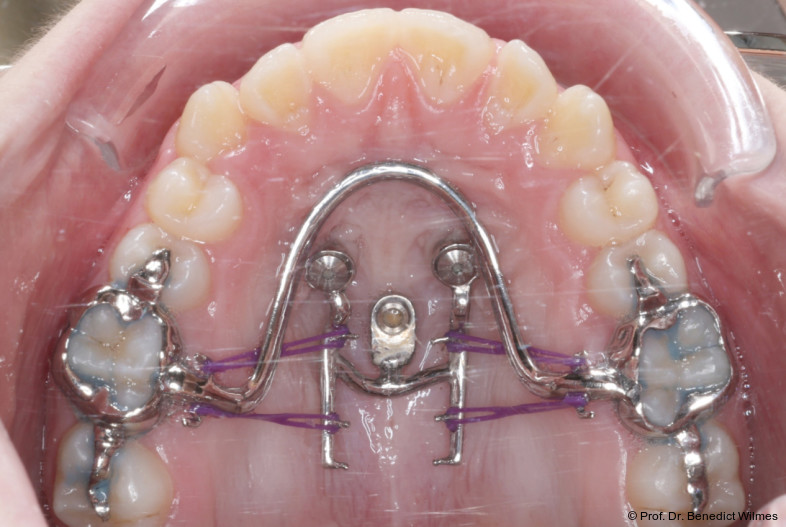

Klinisches Prozedere

Die initiale Behandlung erfolgte mit einer CAD/CAM Hybrid Hyrax zur Expansion des Oberkiefers, verankert an zwei paramedianen Miniimplantaten (Abb. 4, Benefit, 2,0 x 9,0 mm). Anstelle klassischer Molarenbänder wurden Shells (geklebte Kappen) verwendet, wodurch die beiden Schritte Separieren und Anpassen von Molarenbändern entfallen. Die Miniimplantate und die Apparatur wurden dank eines Inser­tionsguides in nur einer Sitzung eingesetzt.

Die Shells wurden mit lichthärtendem Kom­posit befestigt. Nach Expansion des Oberkiefers (Abb. 5a–f) erfolgte eine Retentionsphase von neun Monaten, in der die Hybrid Hyrax in situ belassen wurde.

Nach dieser Rentionszeit wurde die Hybrid Hyrax entfernt und ein Scan zur Herstellung der Molarenintrusionsapparatur (digitale Mause­falle) durchgeführt. Die beiden Miniimplantatköpfe lassen sie dabei sehr gut scannen, so­genannte Scan-Bodies sind in der Regel nicht mehr notwendig. Die digitale Mousetrap-­Appa­ratur besteht aus zwei Teilen (Abb. 6):